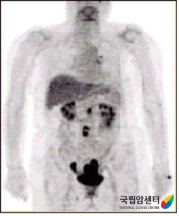

양전자방출단층촬영(PET)

암세포의 대사를 영상화함으로써 암의 유무 및 분포를 보여주는 최첨단 검사입니다. 전신을 촬영하며 암조직이 정상조직에 비해 뚜렷하게 나타나는 장점이 있고, 다른 검사로 찾기 어려운 원격전이, 재발 등을 밝히는데 도움이 됩니다.

골반림프절, 복부림프절에 종양세포의 전이가 있는 자궁경부암 환자의 PET 소견 이미지

[골반림프절, 복부림프절에 종양세포의 전이가 있는 자궁경부암 환자의 PET 소견]